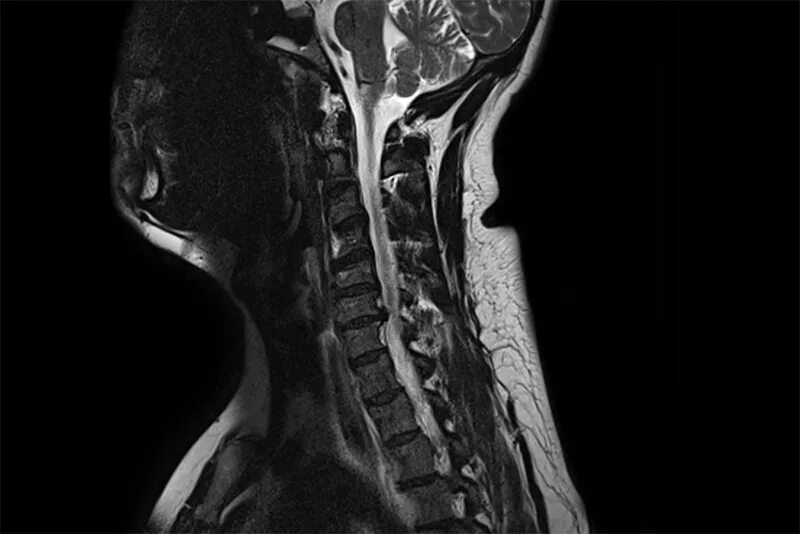

Сколько по времени делается мрт шейного отдела